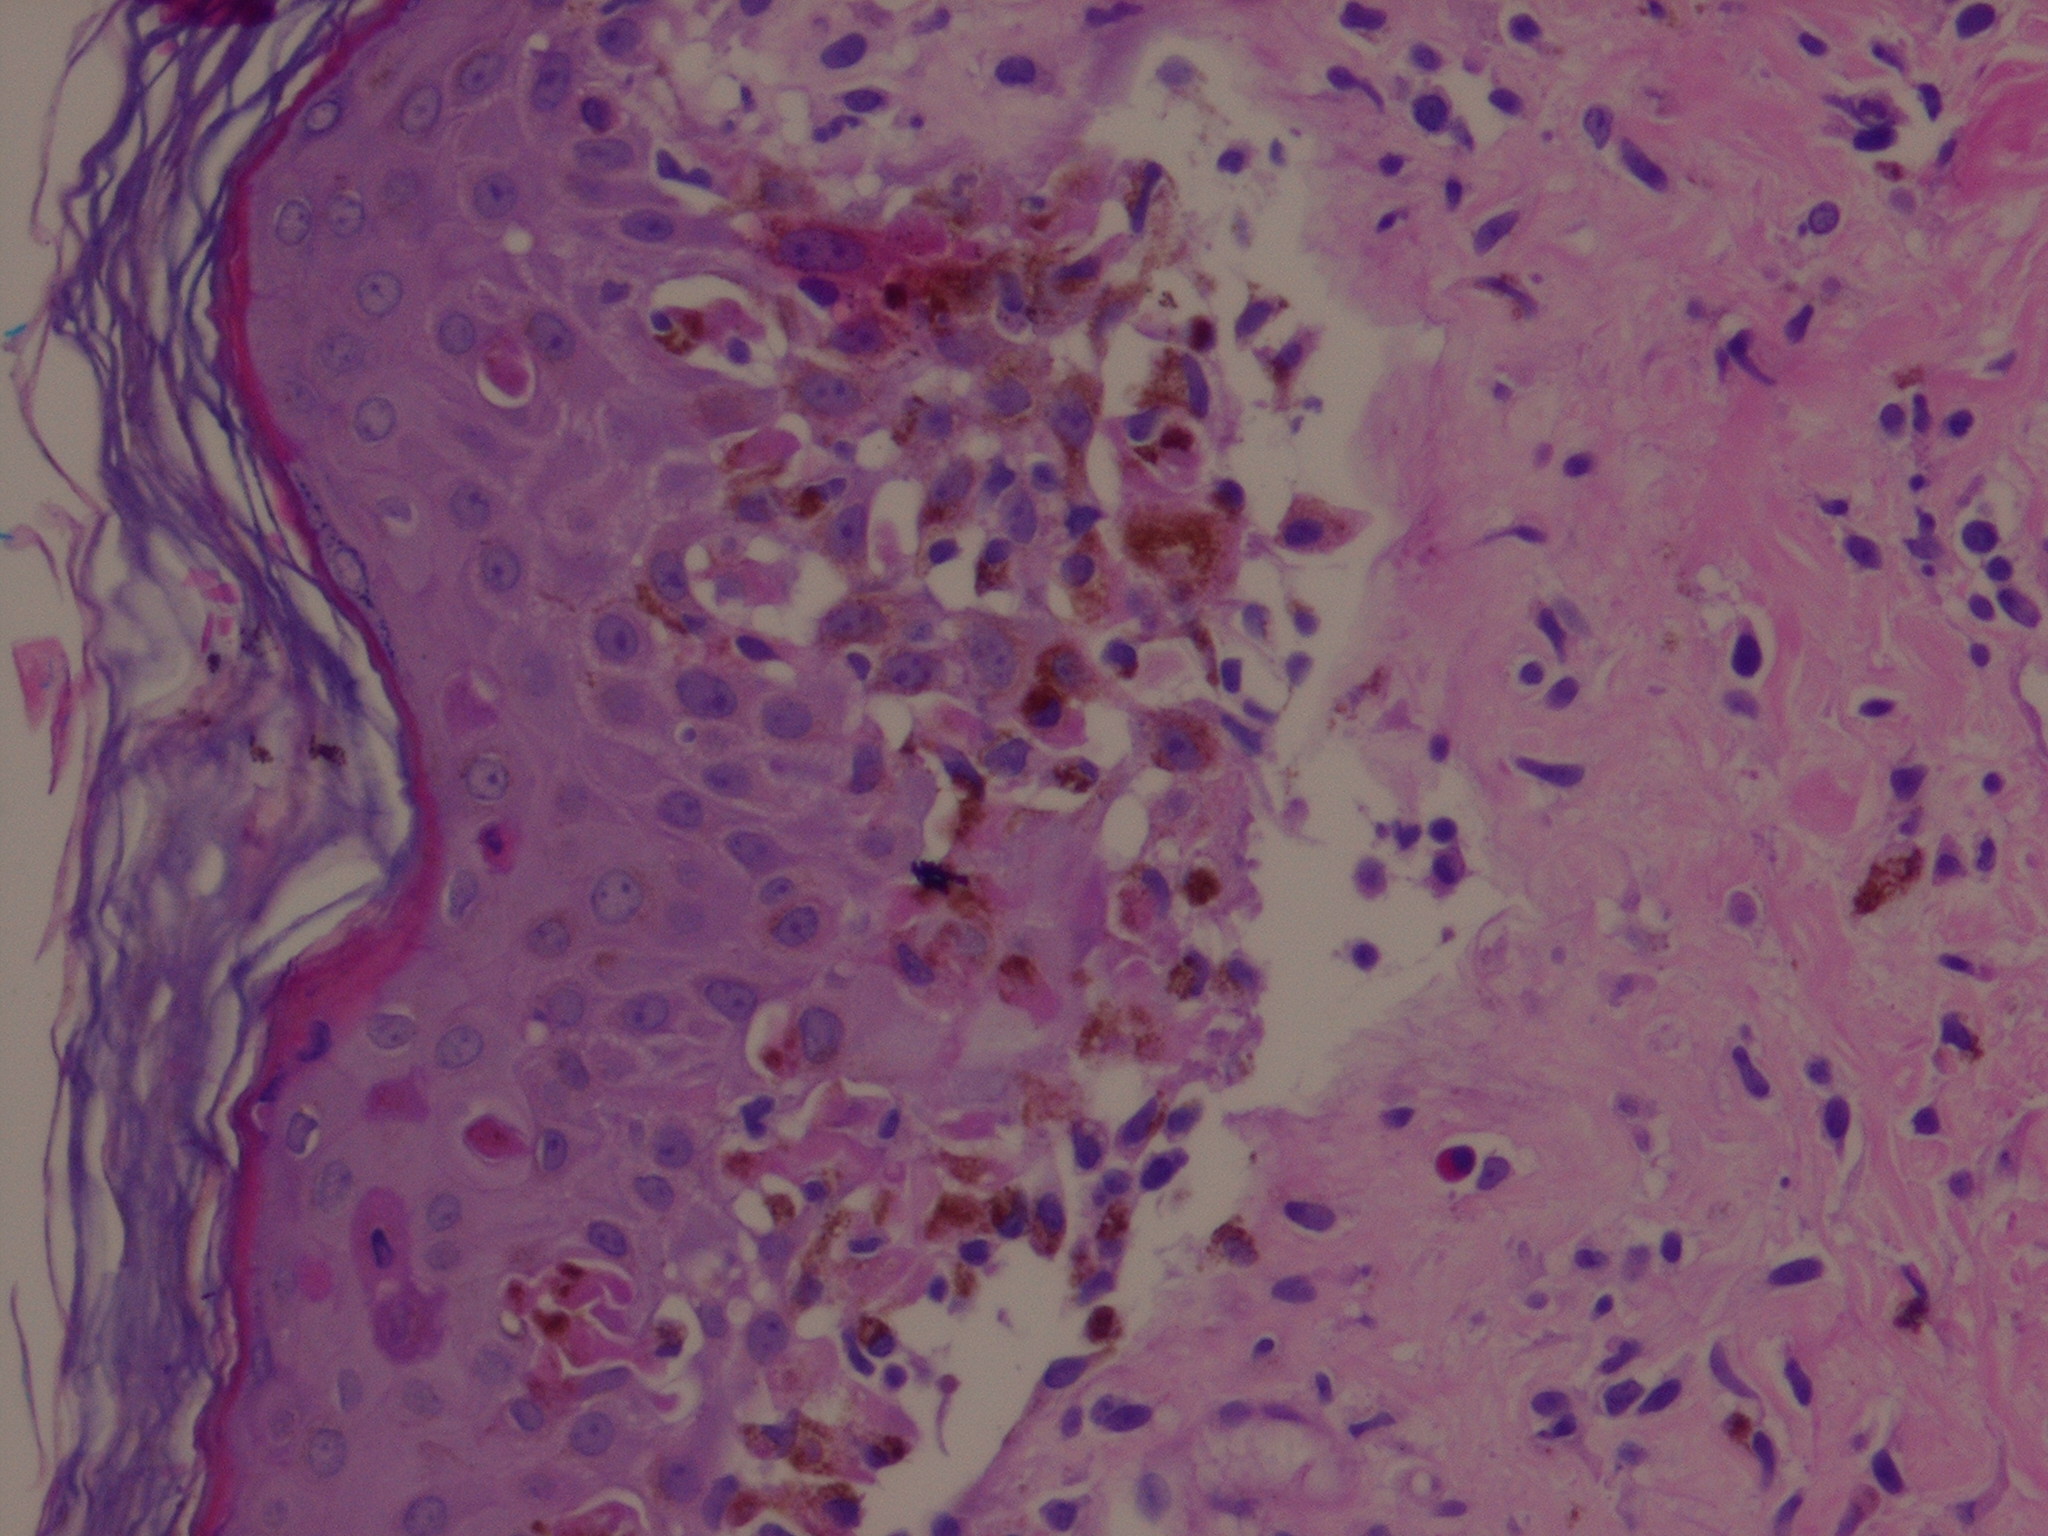

Early lesions of EM exhibit lymphocyte accumulation at the dermal-epidermal interface, with exocytosis into the epidermis, lymphocytes attached to scattered necrotic keratinocytes (satellite cell necrosis), spongiosis, vacuolar degeneration of the basal cell layer, and focal junctional and sub-epidermal cleft formation . The papillary dermis may be edematous but principally contains a dense mononuclear cell infiltrate, which is more abundant in older lesions. The vessels are ectatic with swollen endothelial cells; there may be extravasated erythrocytes and eosinophils. Immunofluorescence findings are negative or non-specific. In advanced lesions sub-epidermal blister formation may occur, but necrosis rarely involves the entire epidermis . In late lesions, melanophages may be prominent.

The histopathologic appearance of EM lesions is different from that of SJS-TEN lesions, in which dermal inflammation is moderate to absent and epidermal necrosis much more pronounced . Still, the histopathologic appearances are somewhat overlapping and do not allow the distinction of EM from SJS-TEN in all instances. The main reason for performing a biopsy is to rule out other diagnoses.